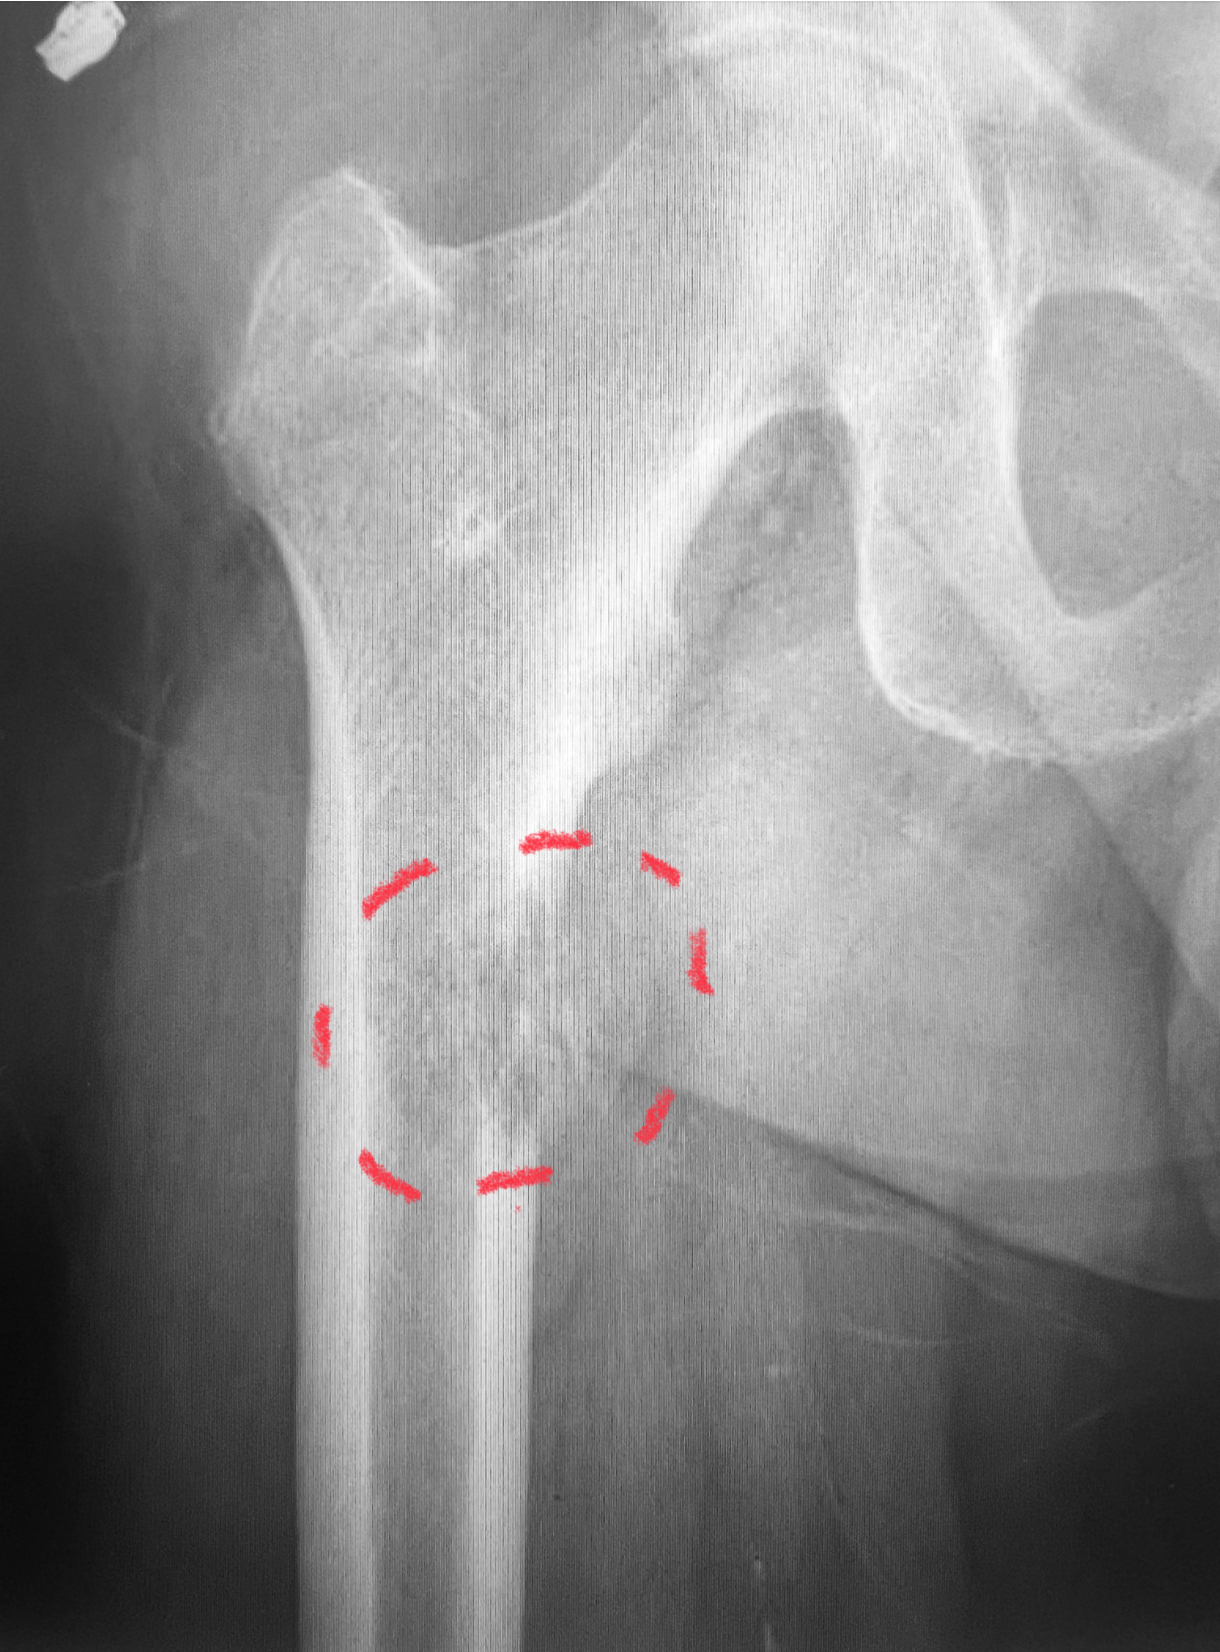

🔹 1. Osteosíntesis profiláctica: prevenir la fractura antes de que ocurra

Cuando la metástasis debilita mucho el hueso, existe riesgo de que se fracture incluso con movimientos cotidianos. En estos casos, podemos colocar un clavo (osteosíntesis profiláctica) para reforzar el hueso y evitar la fractura.

👉 Ejemplo: una metástasis en el fémur que está debilitando más del 50% del hueso.

Metástasis ósea lítica con alto riesgo de fractura patológica